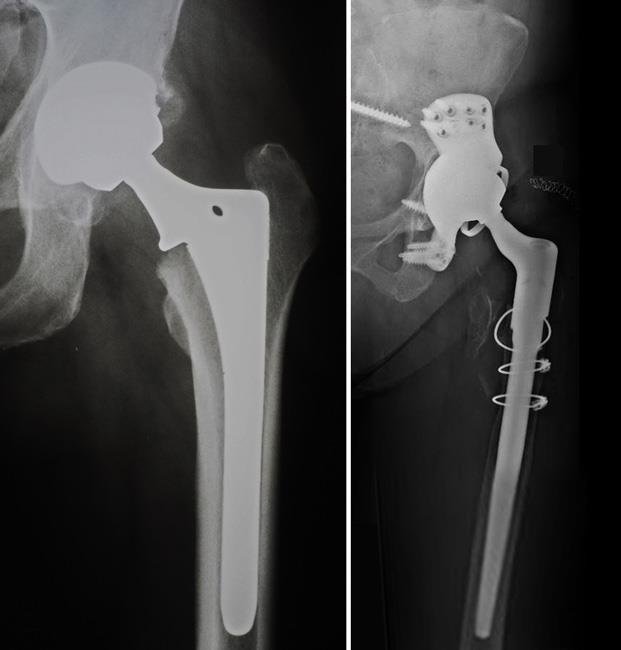

يخضع المريض للفحص السريري ويقوم الطبيب بتحريك المفصل لمعرفة مدى مجال حركته. ويطلب الطبيب صور أشعة لتبيان حالة المفصل ومعرفة المشكلة المتسببة في ظهور الألم عند المريض. ويظهر كل من المفصل الصناعي والعظام بوضوح في أشعة إكس (الأشعة السينية X ).

بينما تظهر الأربطة والعضلات والأنسجة المحيطة بالمفصل في أشعة الرنين المغناطيسي. وقد يطلب الطبيب أشعة مقطعية لضمان صور أكثر دقة للعظام ومعرفة أية تغيرات طرأت عليها. يستعين الطبيب أيضًا بالتحاليل التي تثبت أو تنفي وجود عدوى بكتيرية.

وصف جراحة إعادة استبدال مفصل الفخذ الصناعي

عملية إعادة استبدال مفصل الفخذ للمرة الثانية أكثر تعقيدًا من جراحة تركيب المفصل الصناعي للمرة الأولى.

حيث يقوم الجراح بإزالة المفصل الصناعي وإزالة أية أجزاء تعرضت للكسر أو التفتت وقد يحتاج الطبيب إلى إعادة بناء أجزاء من العظام عن طريق ترقيع العظام, وكذلك إزالة أو إصلاح أي أنسجة متضررة حول المفصل.

كما يستخدم الطبيب أدوات ومواد خاصة بإعادة استبدال المفصل للحصول على نتائج جيدة قدر الإمكان، فنتيجة تركيب مفصل صناعي للمرة الثانية ليست مبهرة مثل تركيبة للمرة الأولى. ولا نقول هنا أن نسبة نجاح الجراحة متدنية، ولكن تنخفض التوقعات فيما يخص أداء المفصل الصناعي الثاني مقارنًة بالأول.

تركيب المفصل

يقوم الطبيب بتركيب المفصل الصناعي الجديد. وقد يتطلب الأمر استخدام العديد من المسامير لتثبيت الحُق الجديد في مكانه. يختبر الطبيب حركة المفصل لضمان ثبات المفصل الصناعي والتأكد من استقرار رأس الفخذ بداخل الحُق.

وتتعدد تصميمات المفصل الصناعي وكذلك تتعدد المواد المصنوع منه المفصل ما بين المعدن والسيراميك والبلاستيك. ويقوم الطبيب باختيار تصميم المفصل المناسب والمادة المصنوع منها بما يتلائم مع حالة المريض. وللاطلاع على كيفية تركيب المفصل وأنواعه ندعوكم لقراءة مقال عن تركيب مفصل الفخذ (الورك) الصناعي.